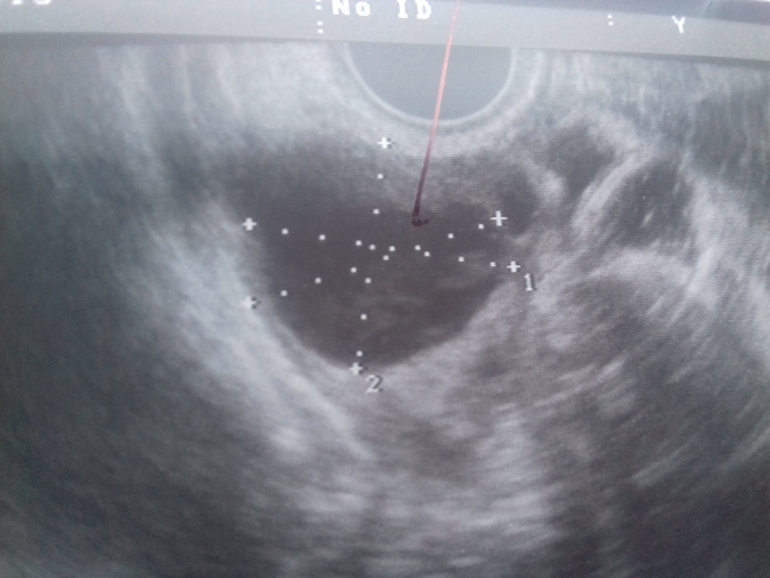

Как отличить кисту ЖТ от фолликулярной?

Какая это киста?

Вам уже верно написали, что определить можно по наличию/отсутствию кровотока. Но к сожалению, не все узисты это смотрят... И пишут потом прост киста, не уточняя какая. По фото можно предположить только, да и то сомнительно. Обычно фолликулярная киста прям темная, почти черная, киста жт - серая с неровными краями. Но это субъективно все.

На фото явно киста желтого тела, она имеет характерное строение, структуры ( ячеистая), фолликулярная киста такой не бывает.

Мне врач несколько раз показывала кисту жт, она всегда как будто сеточкой была, но по фото это нельзя определить, нужно ещё жидкость смотреть и кровоток